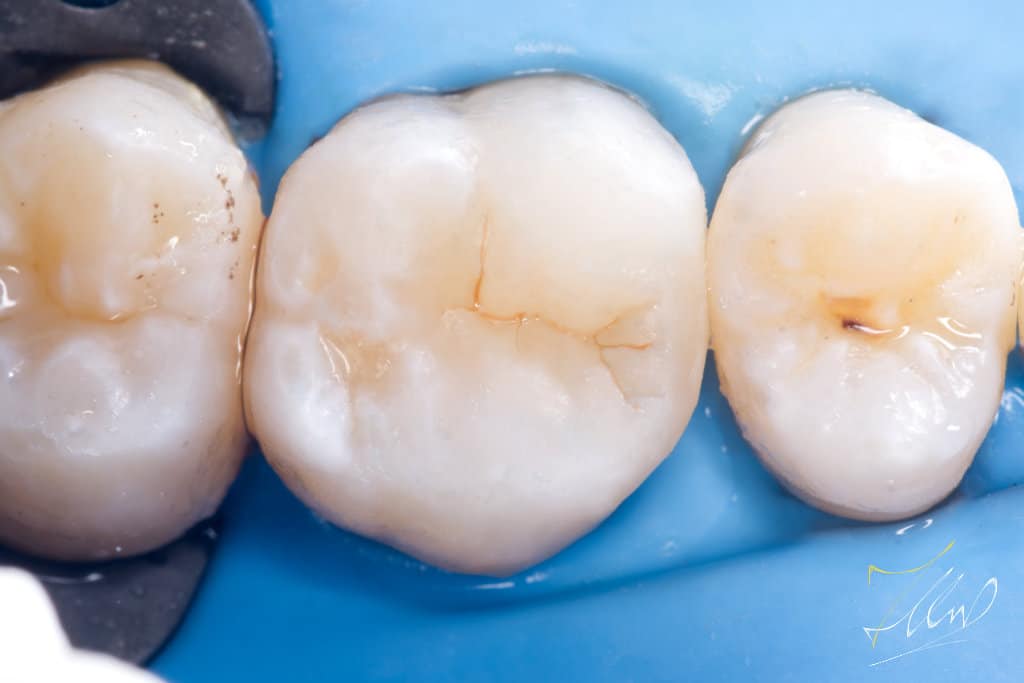

Final cavity design.